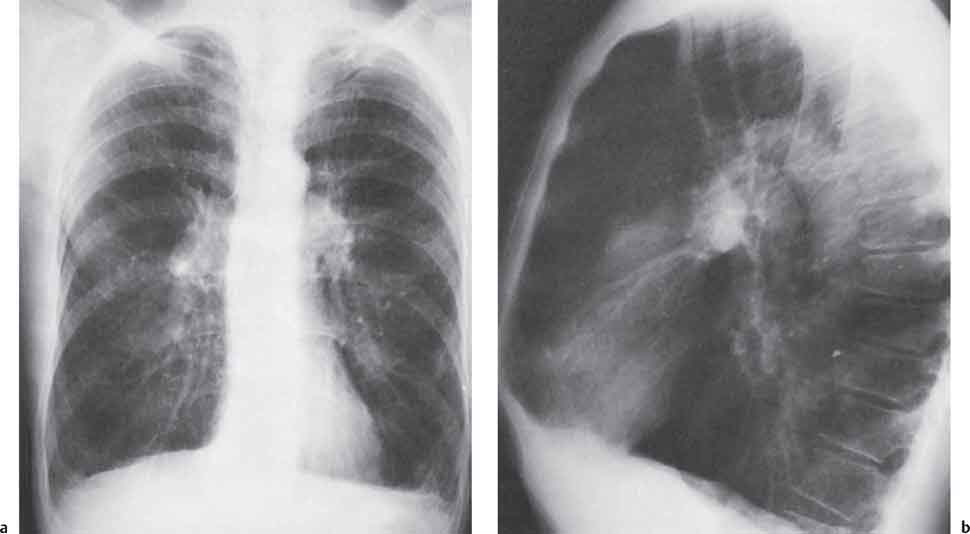

Рентгеновские снимки при врожденной эмфиземе легкого

Раздел: Визуальные уроки